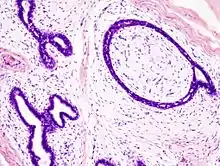

| Histopathologic image of breast fibroadenoma. Core needle biopsy. H&E stain. | |

Fibroadenoma of the breast is a benign tumor composed of a biplastic proliferation of both stromal and epithelial components.[14][15] This biplasia can be arranged in two growth patterns: pericanalicular (stromal proliferation around epithelial structures) and intracanalicular (stromal proliferation compressing the epithelial structures into slit-like spaces).

These tumors characteristically display hypovascular stroma compared to malignant neoplasms.[16][17][11] Furthermore, the epithelial proliferation appears in a single terminal ductal unit and describes duct-like spaces surrounded by a fibroblastic stroma. The basement membrane is intact.[18]

Fibroadenoma histology (H&E). The image demonstrates intracanalicular morphology (bottom left) and pericanalicular morphology (top right)

Histopathologic image of breast fibroadenoma. Core needle biopsy. Hematoxylin & eosin stain.

Histopathologic image of breast fibroadenoma showing proliferation of intralobular stroma compressing and distorting the epithelium. H&E stain.